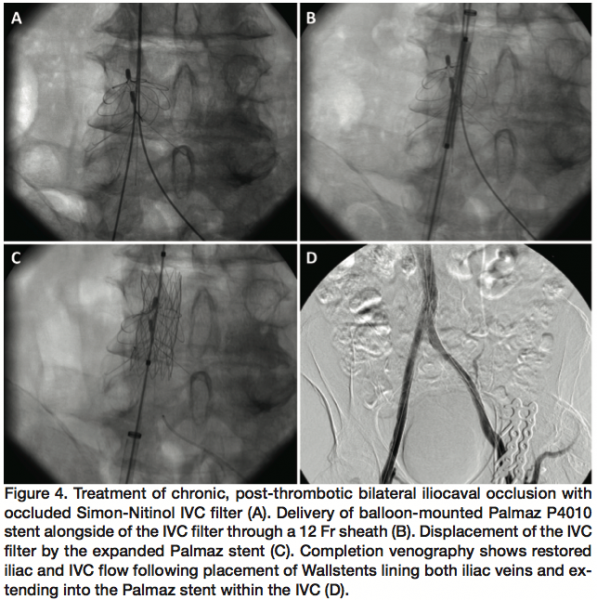

There is no single, reliable non-invasive test to diagnose hemodynamically significant proximal venous obstruction. Venous duplex ultrasonography is useful in evaluating the lower extremities but up to 1/4 of patients with CVD symptoms show little or no ultrasound abnormalities below the groin.17 This subset of patients in particular requires evaluation of the iliac veins and IVC where ultrasound is less reliable, especially in obese patients or due to overlying bowel gas. Computed tomography (CT) scans and magnetic resonance venography scans can be obtained to look for vascular asymmetry, presence of collateral veins, or masses (Figure 1). Though these studies can be very helpful,18 the lack of these findings does not rule out a flow-obstructing lesion. If a CT scan is obtained, delayed venous phase images should be requested for the most helpful diagnostic information.